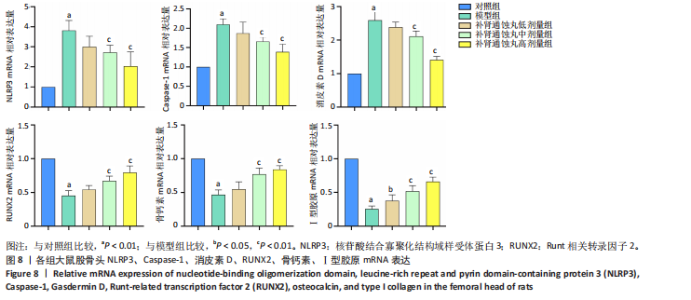

素D-N蛋白表达均显著上调(P < 0.01),成骨因子Runt相关转录因子2、骨钙素、Ⅰ型胶原蛋白表达均显著下调(P < 0.05);补肾通蚀丸各剂量组NLRP3、cleaved-Caspase-1、Caspase-1、消皮素D、消皮素D-N蛋白表达以一定剂量依赖方式呈现不同程度的下调,Runt相关转录因子2、骨钙素、Ⅰ型胶原蛋白表达则以一定剂量依赖方式呈现不同程度的上调;与模型组比较,补肾通蚀丸中、高剂量组NLRP3、cleaved-Caspase-1、Caspase-1、消皮素D、消皮素D-N蛋白表达均显著下调(P < 0.05),补肾通蚀丸高剂量组Runt相关转录因子2、骨钙素、Ⅰ型胶原表达均显著上调(P < 0.01),补肾通蚀丸中剂量组Runt相关转录因子2蛋白表达显著上调,而骨钙素、Ⅰ型胶原表达无明显差异(P > 0.05),补肾通蚀丸低剂量组Runt相关转录因子2、骨钙素、Ⅰ型胶原表达均无明显差异(P > 0.05),见图7A,B。与对照组比较,模型组cleaved-Caspase-1/Caspase-1比值和消皮素D-N/消皮素D比值均显著上升(P < 0.01);与模型组比较,补肾通蚀丸中、高剂量组cleaved-Caspase-1/Caspase-1比值和消皮素D-N/消皮素D比值均显著下降(P < 0.01),而补肾通蚀丸低剂量组cleaved-Caspase-1/Caspase-1比值与对照组比较无明显差异(P > 0.05),见图7C。 2.7 RT-qPCR检测结果 RT-qPCR结果显示,与对照组比较,模型组大鼠股骨头组织中NLRP3、Caspase-1、消皮素D mRNA表达显著上调,Runt相关转录因子2、骨钙素、Ⅰ型胶原mRNA表达显著下调(P < 0.01);与模型组比较,补肾通蚀丸中、高剂量组NLRP3、Caspase-1、消皮素D mRNA表达均显著下调,Runt相关转录因子2、骨钙素、Ⅰ型胶原mRNA表达均显著上调(P < 0.01),而补肾通蚀丸低剂量组NLRP3、Caspase-1、Runt相关转录因子2、骨钙素mRNA表达均无明显差异(P > 0.05),见图8。"